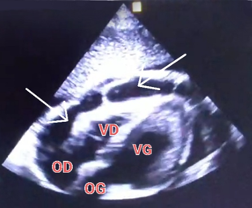

A male patient aged 23, on automated peritoneal dialysis since 2021 (APD: total volume 10 L, 4 cycles of 2 h, injection volume 2 L, final stasis 1 L, concentrations 2.27%). The measured dialysis dose was a total Kt/V of 1.35 and a WCCr of 38 L/week/1.73 m2, nPCR at 0.85. One week prior to admission, the patient presented with non-radiating retrosternal chest pain with dyspnea. An ECG and chest X-ray were performed, which came back unremarkable. With worsening chest pain and dyspnea, the patient was admitted to the emergency department. Clinical examination revealed tachycardia at 115 bpm, BP 140/90 mmHg, apyrexia, decreased heart sounds, orthopnea, SpO2 of 95% on room air, no crepitus rales, and no signs of right heart failure. ECG showed diffuse microvoltage. Chest X-ray revealed cardiomegaly (ICT 0.7) with hilar overload (Figure 3.). TTE showed a large circumferential pericardial effusion at 23 mm without collapse, with fibrin deposits, dilated IVC, and 50% LVEF (Figure 4.). A biological inflammatory syndrome was present, with CRP of 160 mg/L without hyperleukocytosis, and negative troponin 28 ng/dL. The patient underwent emergency pericardiocentesis, yielding 500 mL of hematic, exudate fluid (protein 56 g/L). Cytobacteriological examination, BK testing, and GeneXpert in the puncture fluid were negative, with no cells suspected of malignancy on pathology.

Figure 4.Subcutaneous TTE section showing a large pericardial effusion with fibrin